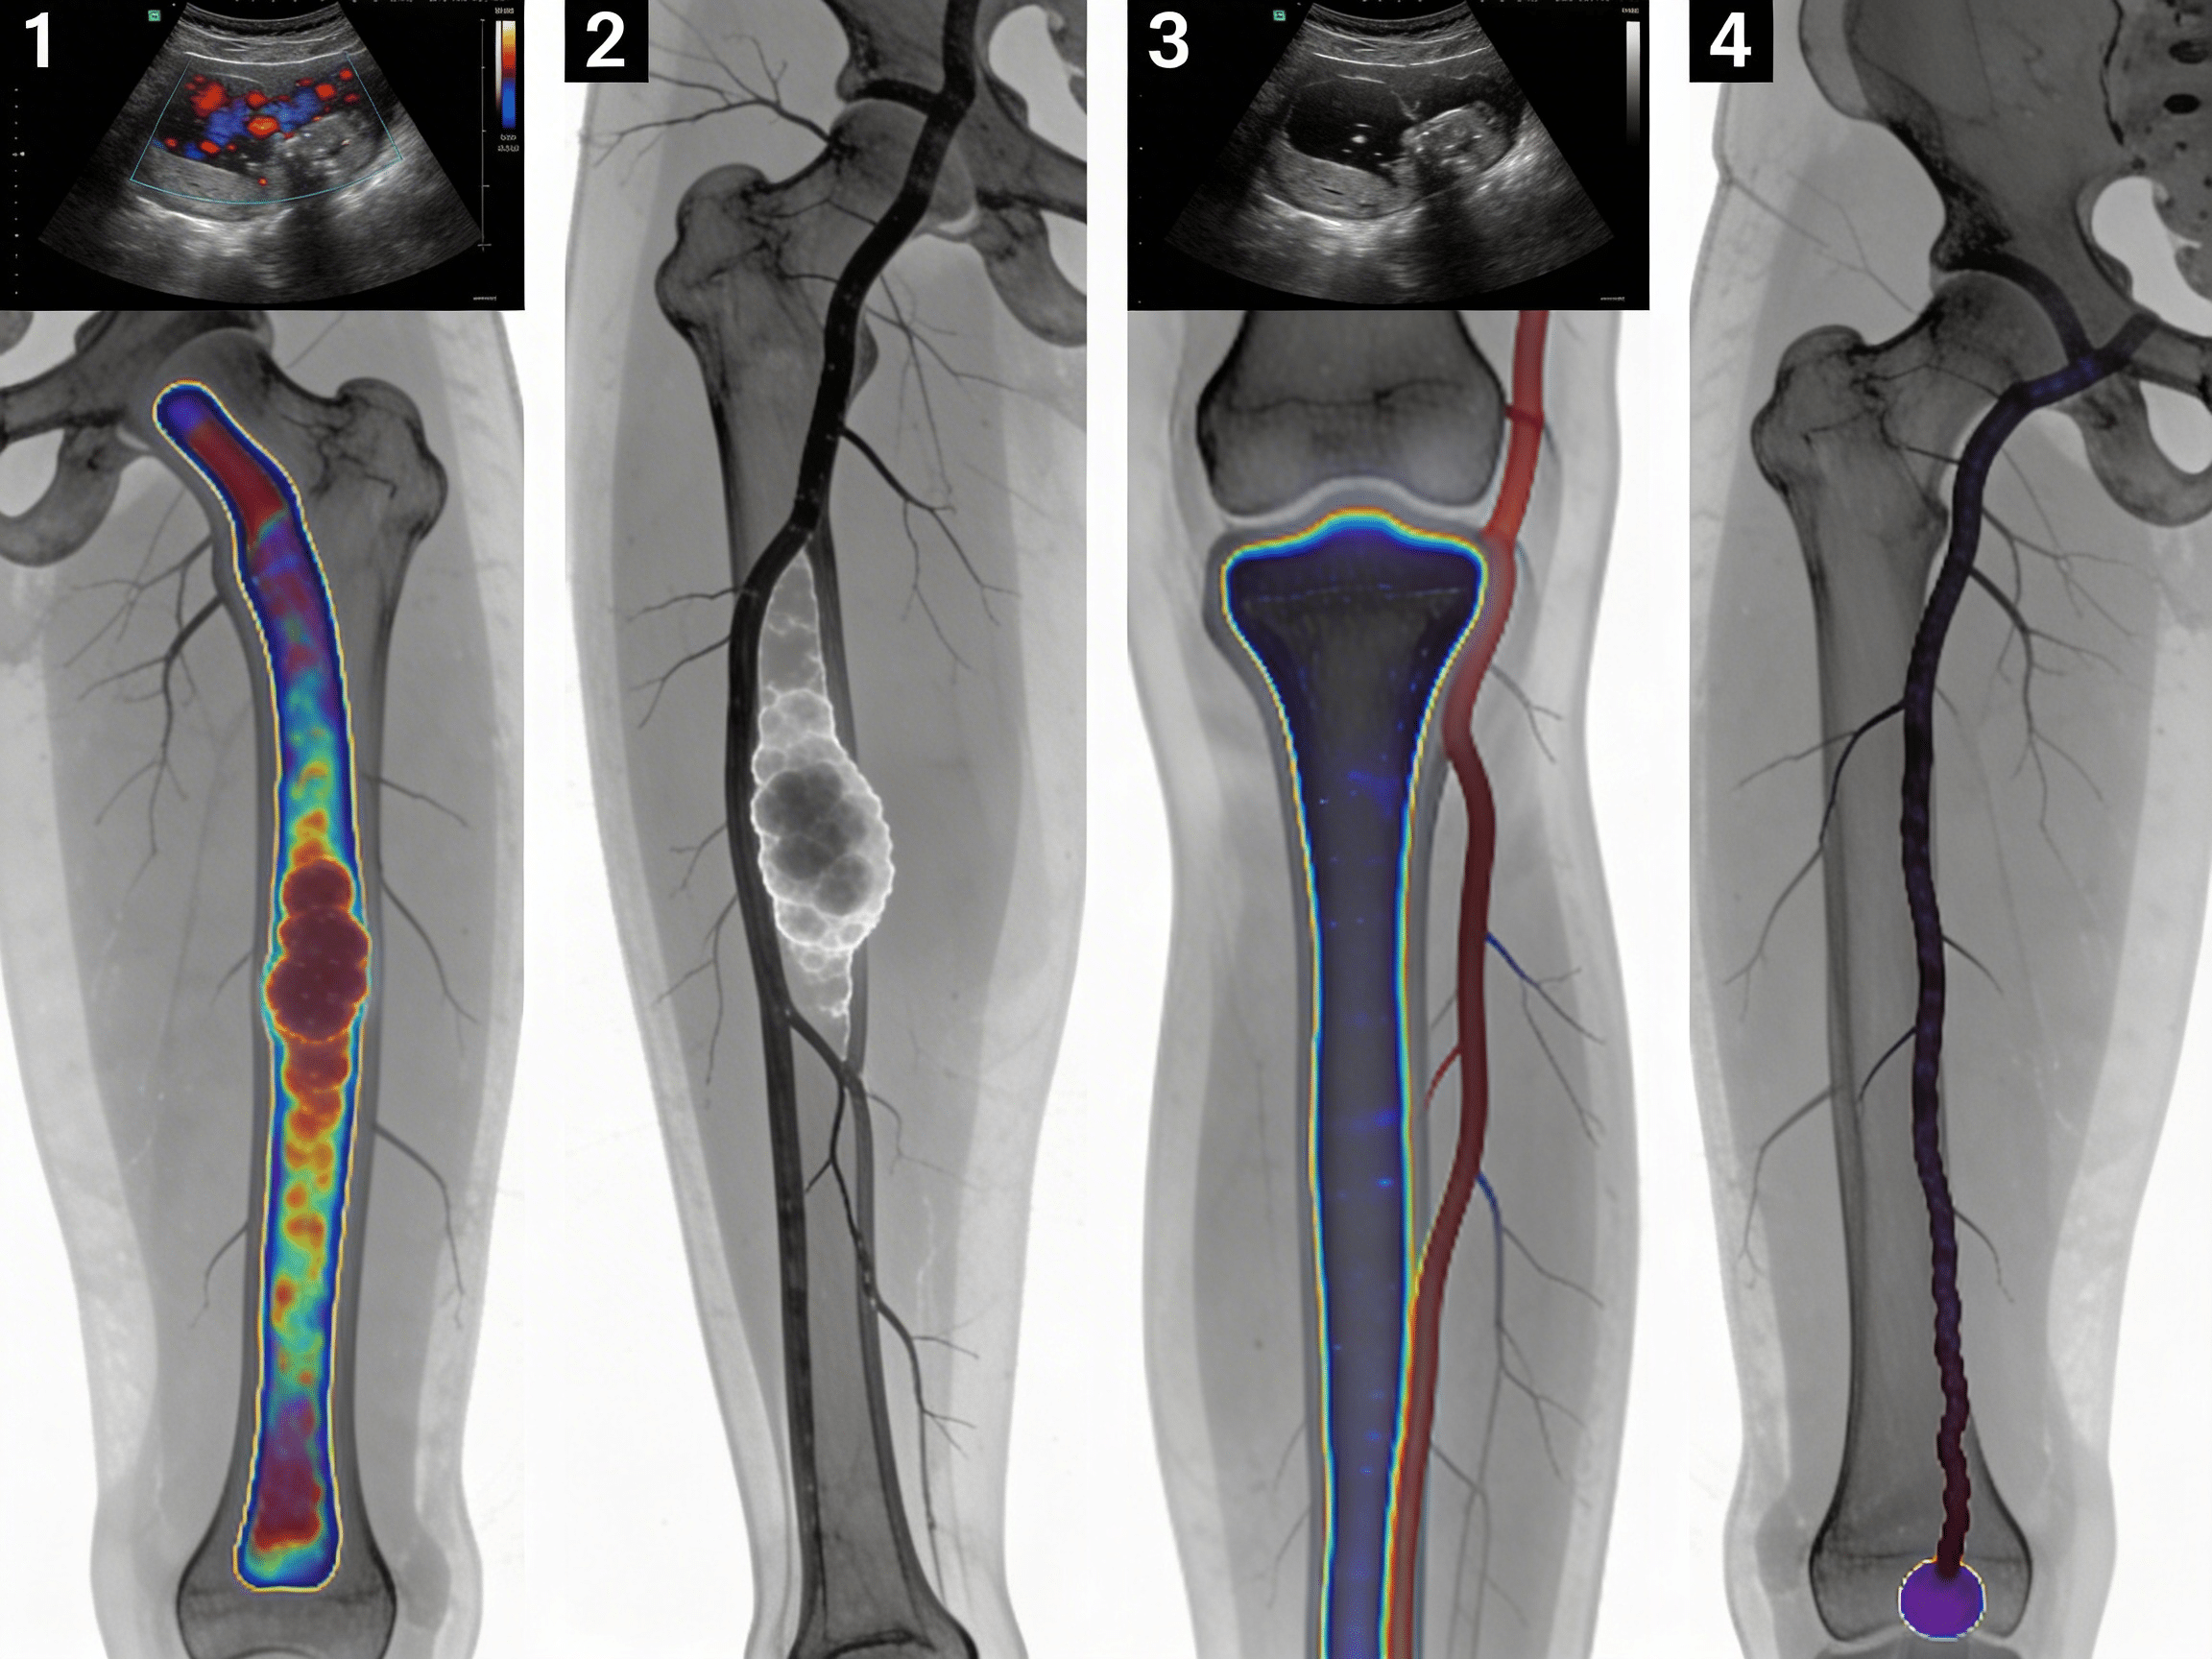

West Texas DVT Risk Patterns Requiring Vascular Imaging

West Texas presents unique DVT risk patterns that residents of Odessa, Midland, and surrounding Ector County communities face daily. The region's extensive oil and gas industry creates perfect conditions for deep-vein thrombosis, with prolonged sitting, dehydration, and industrial work representing 58% of emergency vascular doppler cases[10]. During peak production seasons, Priority ER sees a 245% increase in work-related DVT, with lower extremity thrombosis, post-trauma clots, and obesity-related DVT comprising the majority of diagnostic imaging needs[11].

West Texas Vascular Doppler Cases by DVT Type

The Permian Basin's rough terrain and high-speed rural roads contribute to motor vehicle accidents requiring immediate vascular imaging to rule out traumatic DVT and compartment syndrome[12]. Our trauma emergency capabilities include specialized protocols for multi-trauma patients requiring rapid full-body vascular assessment and CT imaging. Additionally, the region's extreme heat increases dehydration-related DVT by 40% among oil field workers, with calf and femoral vein thrombosis requiring immediate diagnostic imaging to prevent surgical delays[13].

Advanced Vascular Doppler Technology: Beyond Basic Urgent Care

Priority ER's diagnostic capabilities for vascular doppler ultrasound for deep-vein thrombosis exceed Joint Commission standards for emergency departments[14], featuring equipment typically found only in specialized vascular centers. Our duplex doppler system produces images with 30% better resolution than standard urgent care facilities, enabling detection of small thrombi, valve incompetence, and venous obstruction as subtle as 1mm[15]. The integration of PACS (Picture Archiving and Communication System) technology allows instant image transmission to consulting vascular surgeons when complex DVT requires specialized anticoagulation planning.

Advanced imaging through our 64-slice CT scanner provides three-dimensional venous reconstruction within minutes, crucial for identifying clot extent, pulmonary embolism risk, and treatment requirements that standard doppler cannot fully assess. For chest pain cases with leg swelling, our digital imaging system captures both pulmonary and venous studies simultaneously, reducing radiation exposure by 40% while providing comprehensive thrombosis evaluation. This technology gap explains why the American College of Emergency Physicians recommends freestanding ERs over urgent care for all suspected DVT and serious vascular emergencies requiring immediate diagnostic imaging.